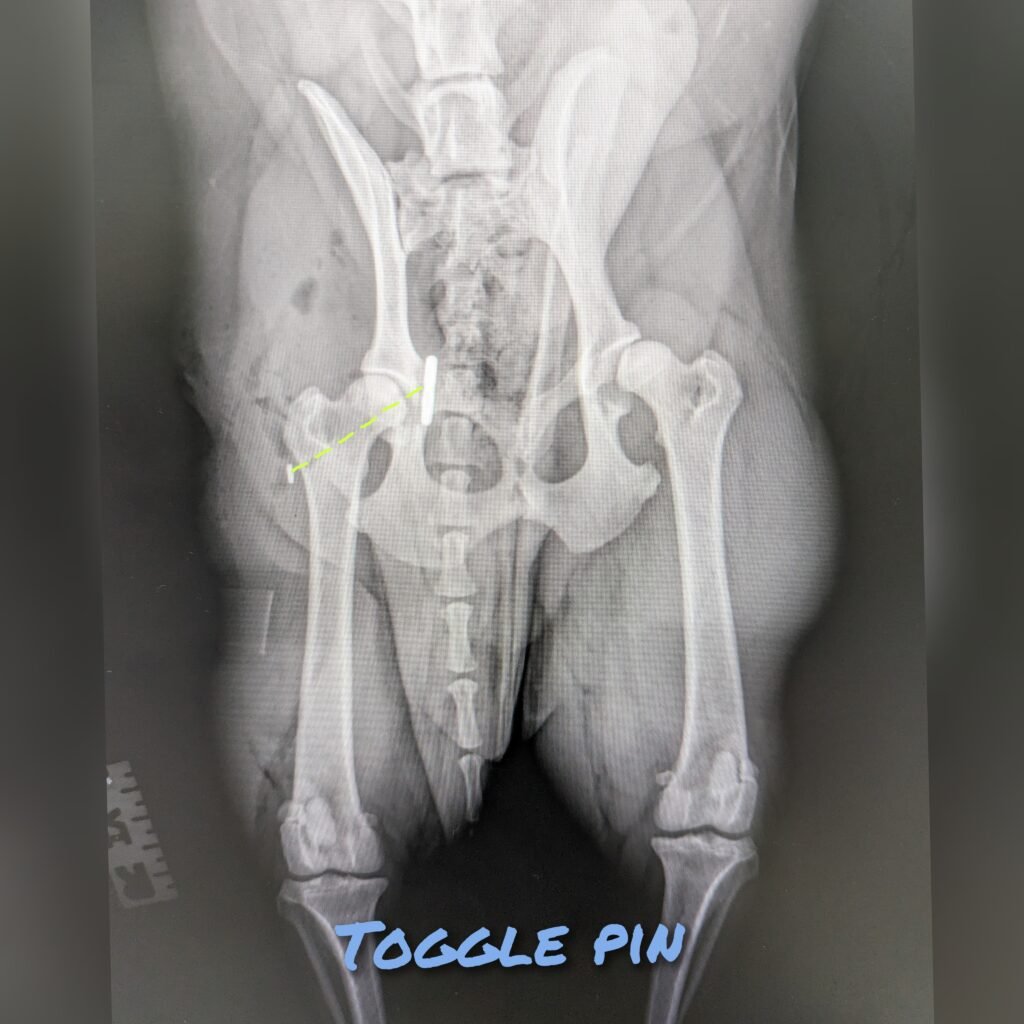

Toggle pin technique involves placing an artificial ligament (Green line) to replace the round ligament and its function. However this technique is only recommended if the patient has normal hip conformation. The hip joints gets preserved unlike salvage procedures. This procedure require more precision and more involved compare to FHNE therefore it usually costs more than FHNE. The implants can fail with enough force and hip luxation can recur. In these cases, salvage procedure can be considered.